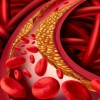

2. Xuất huyết nặng

Do giảm tiểu cầu và rối loạn đông máu.